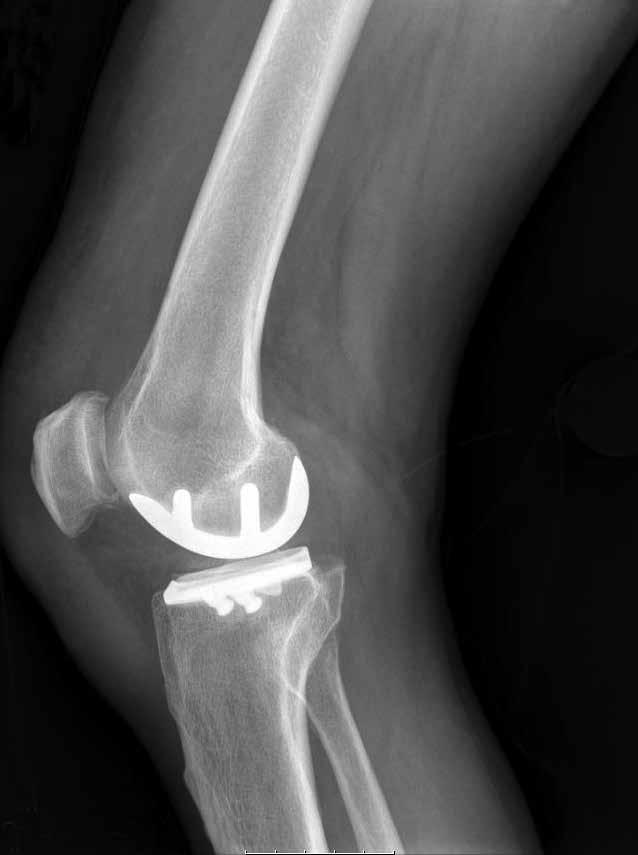

Knee surgery in Texas just got innovative.

Dr. Raul A. Marquez, Orthopedic Surgeon, performs the leading-edge surgery at Cornerstone Regional Hospital using the NAVIO Surgical System™.

Raul A. Marquez, MD

The robotic assistance eliminates the need for a pre-operative CT scan and enables precise and efficient placement of the implant. During the procedure, a 3D model of the patient’s knee is used to guide the robotics-assisted tool directed by the physician, providing an extra layer of precision and accuracy.